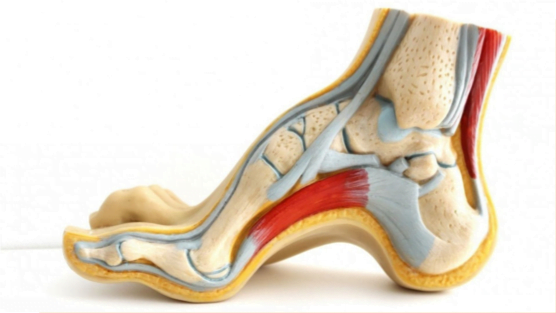

PIE CAVO

Es la elevación anormal del arco longitudinal del pie, que se mantiene al apoyar el pie en el suelo.

¿Qué causa el pie cavo?

La causa más frecuente de los pacientes con el pie cavo es por problemas de los nervios que controlan la movilidad de los músculos del pie, ya sea de origen hereditario, congénito o traumático.

¿Qué cirugías se realizan para tratar el pie cavo?

Dentro de las diversas cirugías que existen para el pie cavo tenemos: las osteotomías en distintos huesos del pie, la liberación de la fascia plantar, las transferencias tendinosas, la reconstrucción de ligamentos, la elongación de tendón de Aquiles, y la fusión entre algunos de los huesos del pie.

¿Cómo sé cuál es la mejor cirugía para mi pie cavo?

Se debe identificar primero la causa del pie cavo, las deformidades asociadas, las principales zonas de dolor y el desgaste de las articulaciones del pie. Ya con esa información se elige que combinación de procedimientos es la más adecuada para tu pie; por esa razón es muy importante acudir con un especialista capacitado en el manejo quirúrgico del pie cavo.